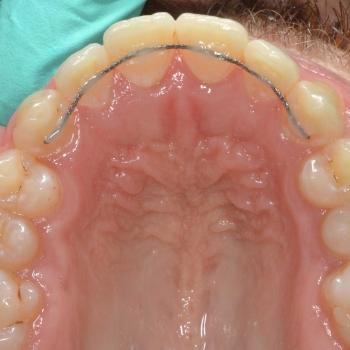

János egy másik fogorvos által befejezett, illetve később részlegesen újrakezdett fogszabályozó kezelés sikertelensége miatt keresett fel rendelőmben. Az első konzultáció alkalmával több esztétikai és funkcionális hibát is észrevettünk, többek között keresztharapást, enyhe nyitott harapást, torlódást, egyoldali Class II harapási eltérést, az alsó és felső őrlőfogak egymással nem harmonizáló dőlését, illetve az alsó középvonal funkció közbeni eltolódását balra.

A kezeléshez János hagyományos fém fogszabályozót választott, melyet kiegészítettünk a legkülönfélébb intermaxilláris gumihúzásokkal, illetve egy speciális belső oldali fogszabályozó ívvel, ami segített az alsó őrlőfogakat a nyelv irányába dönteni.